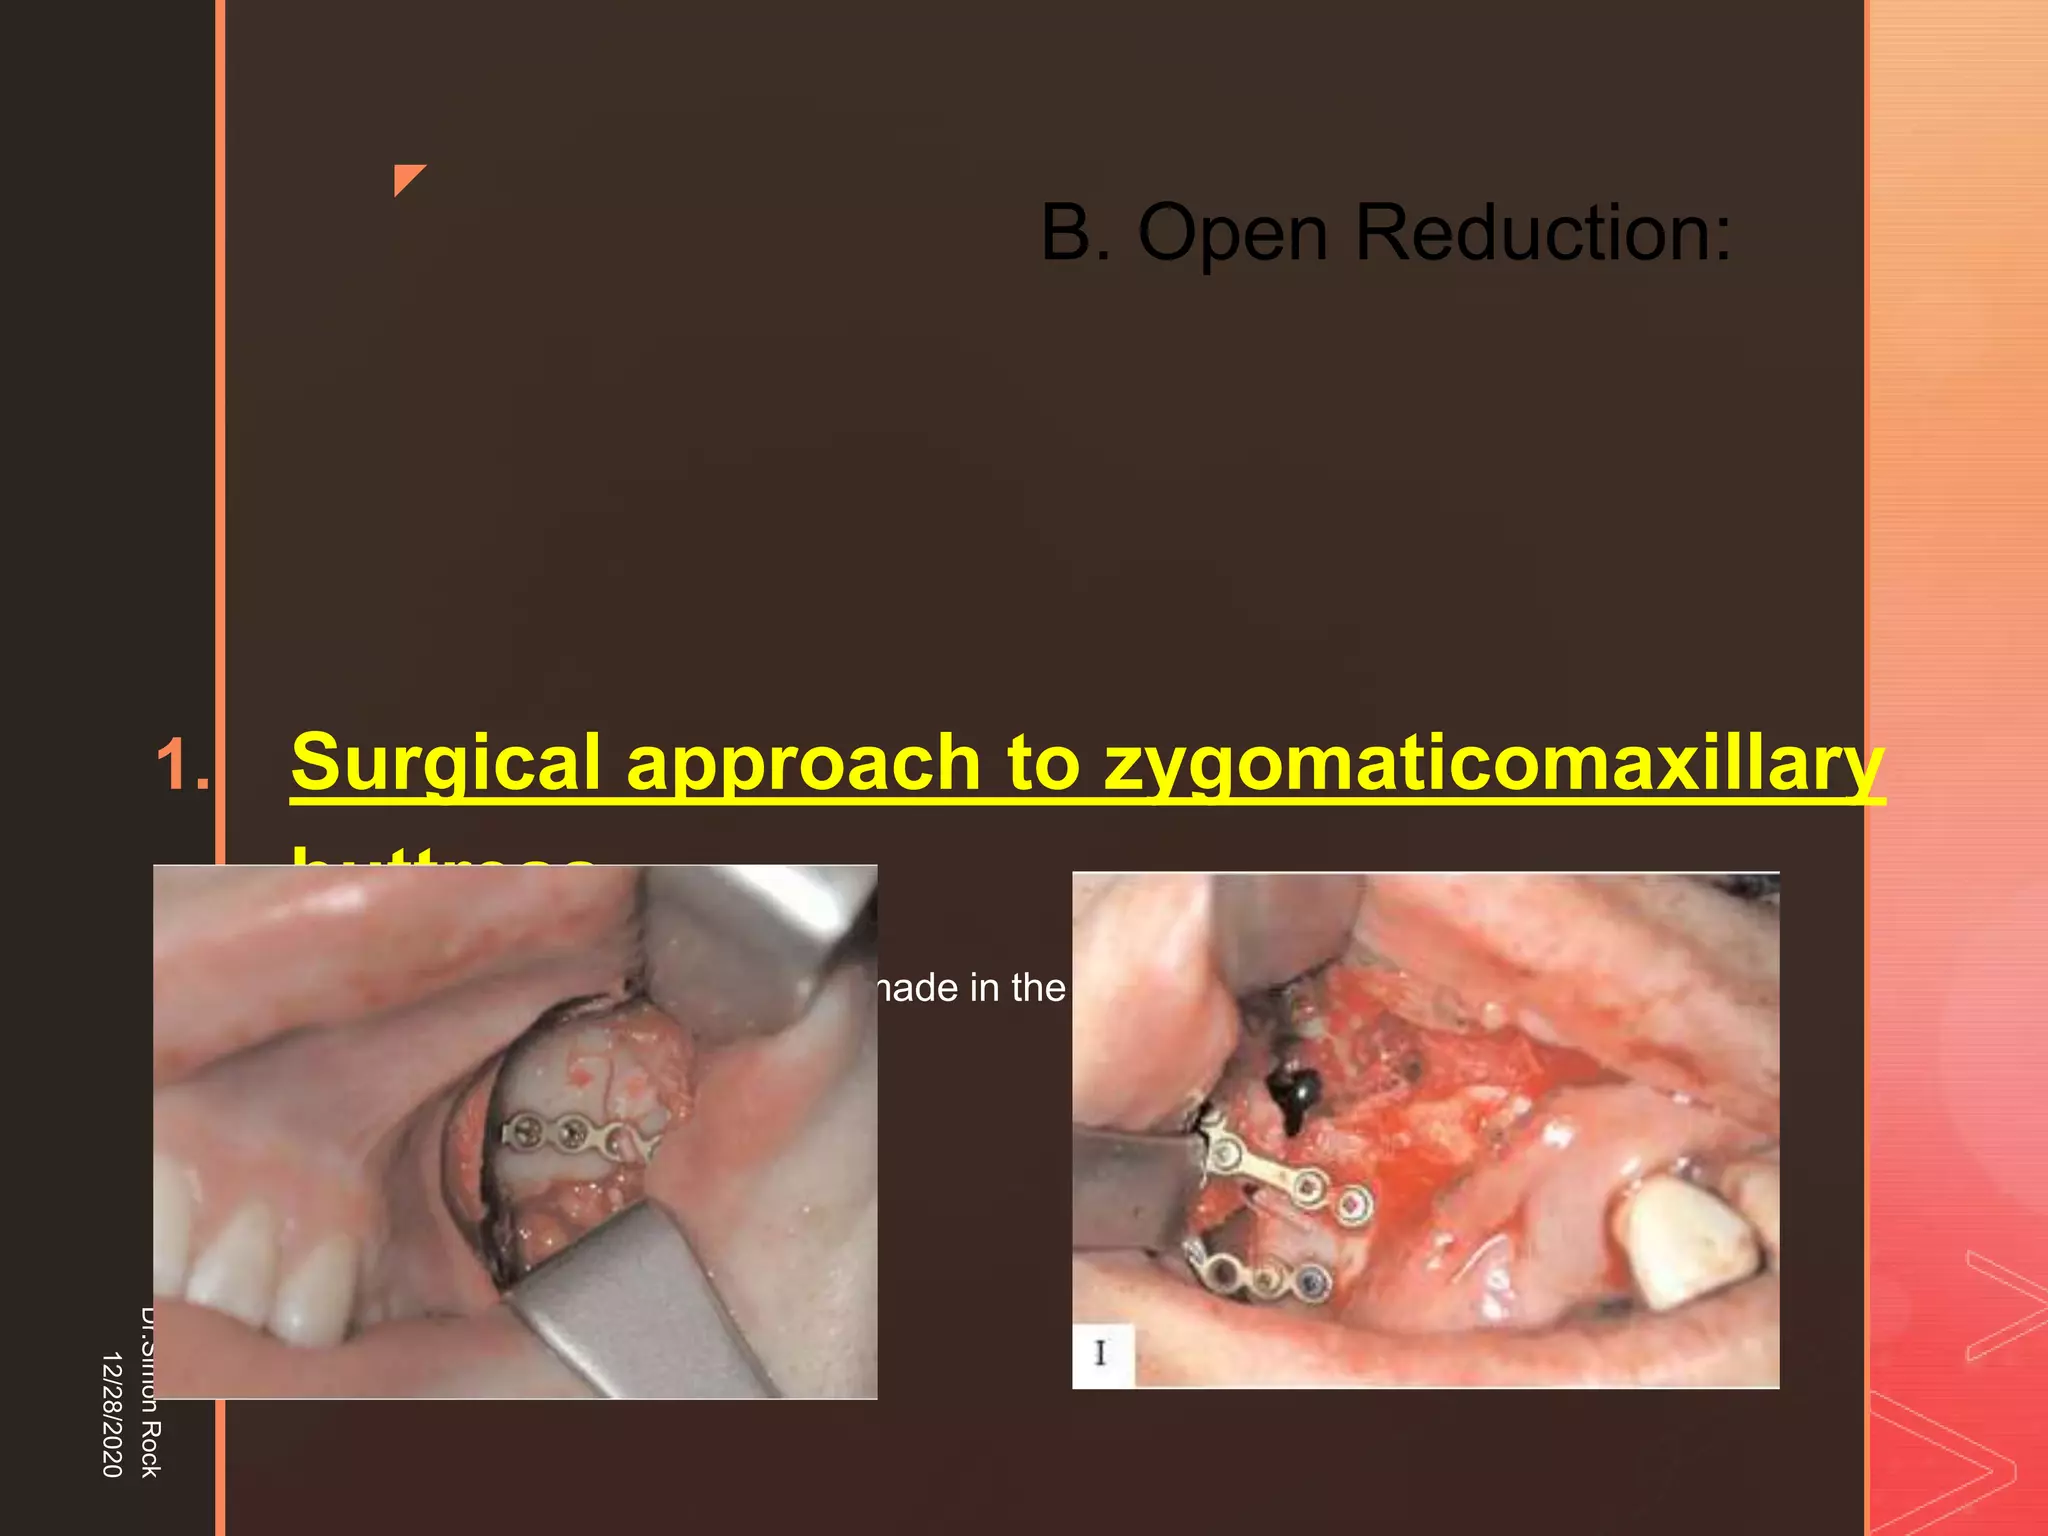

This document discusses the anatomy and fractures of the zygomatic bone. It notes that the zygoma forms the cheekbone and articulates with several other facial bones. Zygomatic fractures most commonly occur in the arch or body due to blunt trauma. Diagnosis involves checking for diplopia, ecchymosis, and other signs of orbital or facial bone involvement. Treatment may involve closed or open reduction based on the severity of displacement. Closed reduction techniques try to elevate the bone back into position without surgery, while open reduction requires surgical exposure and fixation of the fracture site.